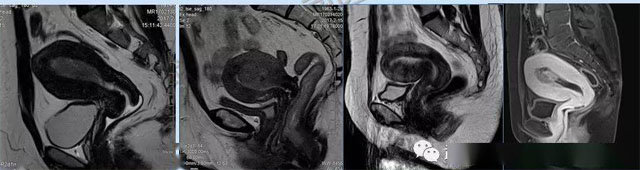

婦科疾病常常讓女性陷入了焦慮。主要是這類疾病婦女有難言之隱,癥狀隱匿,病情復(fù)雜。磁共振體檢車的金光火眼能力可以破解各種婦科難題。哪些情況需要使用磁共振檢查,檢查過程是否有不適。這些都是可以解決的。例如子宮常見疾病的磁共振診斷。

磁共振VS傳統(tǒng)檢查:有這些優(yōu)勢?無輻射安全系數(shù)高,磁共振沒有電離輻射,適合備孕跟孕婦檢查。它對軟組織有高清的成像效果,可以清晰的看到子宮各層的結(jié)構(gòu)。可以識(shí)別細(xì)小的肌瘤,早期的癌癥腫瘤??梢园l(fā)現(xiàn)其他設(shè)備難以檢查到的深部子宮內(nèi)膜異位結(jié)節(jié)。多序列成像和增強(qiáng)掃描檢查,判斷腫瘤的良性準(zhǔn)確率高達(dá)90%以上。